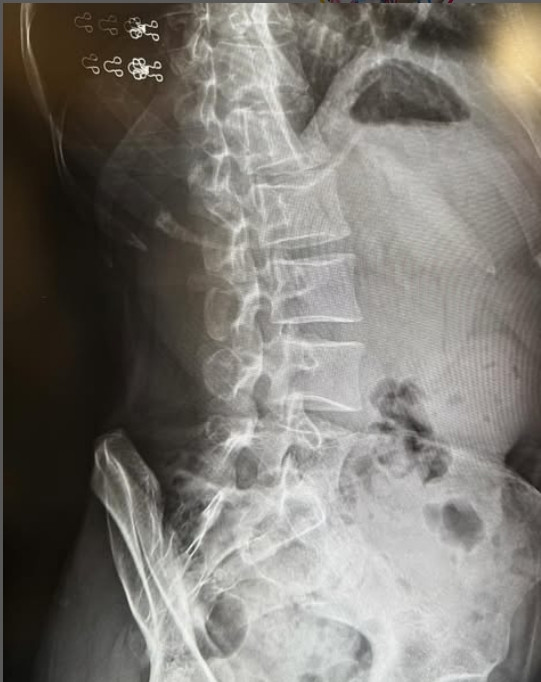

レントゲン写真を公開した新井恵理那(写真はインスタグラム @elina_arai より) (2/2枚)

新井恵理那アナ、35歳で初のぎっくり腰「ピキ!っときまして」「『これか』と思いましたね」